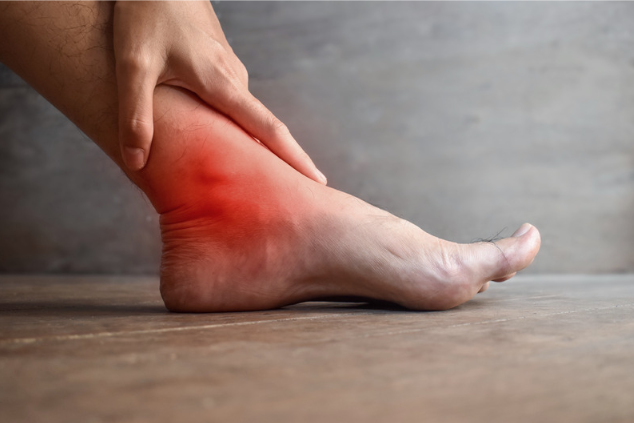

50歳以上では10人に1人が踵痛を自覚していると言われており,多いのが足底腱膜炎です。繰り返しの荷重によるストレスで足の裏側のスジに負担がかかり、炎症を起こして踵の痛みになる病気が足底筋膜炎です。肥満や偏平足、長時間の立位が必要な仕事の方、クッション性の低い靴の使用などがなりやすいと言われています。足底腱膜炎は保存治療で大多数の患者さまがよくなりますが、1~2割が難治性になると言われていますので注意が必要です。

足底筋膜炎の診断

上記の図のように踵の内側に痛みの場所があることが特徴です。またレントゲンで65%の人に踵の棘があると言われております。またエコーで分厚く脹れた足底筋膜を確認できると診断に近づきます。

足底筋膜炎の治療

基本的に保存治療を行い、その中でも運動療法が重要です。アキレス腱および足底腱膜のストレッチングが有効であり,足底腱膜炎に対して第一選択となる治療法です。ストレッチングの頻度・時間などに一致した見解はありませんが、当院では30秒×4回(合計2分間)のアキレス腱ストレッチングを1日1~3回行うことを患者さまに提案しております。高齢者では関節の拘縮があると十分なストレッチング動作を行えないことが多い.その場合,テニスボールやゴルフボールを用いた筋肉マッサージを当院では提案しています。

またサポーターや装具も有効で、踵部に除圧加工を施した足底挿板の使用を薦めています。

炎症を抑える薬や湿布、塗り薬、注射などの併用し治療することもございます。物理療法やリハビリも可能であり、総合的に治療し、痛みを慢性化させないことを目標に治療しています。